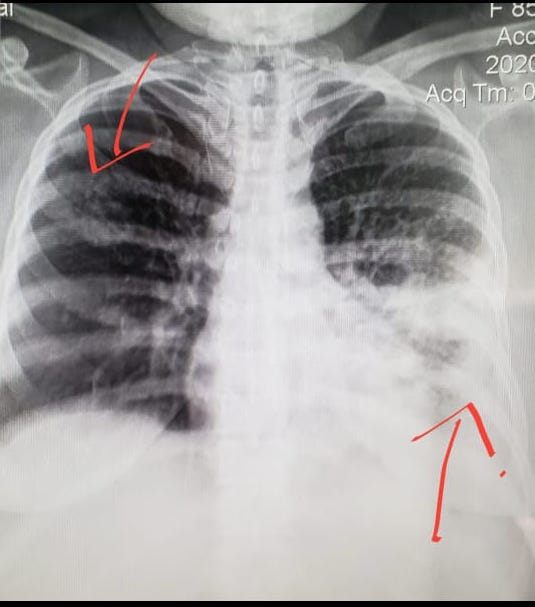

Un mes más tarde, con el pico de contagios en su etapa más álgida, y con la dificultad de matizarlos ante tantos entierros, la vicepresidenta Rosario Murillo admitió un aumento del 54% de muertes por neumonía. Sin embargo, no las asoció al coronavirus. En aquel momento, DIVERGENTES recopiló con fuentes médicas más de cincuenta radiografías de pulmón de diversos hospitales del país, en la que los casos neumónicos eran evidentes. Los doctores aseguraron que no les cabía duda de que se trataban de casos de COVID-19, pero la mordaza impuesta por la autoridad sanitaria y la centralización de las pruebas impedían alertar a los familiares de los contagiados. Médicos sostienen que haber minimizado el impacto de la pandemia, generó más contagios y muertes.